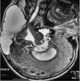

Intradiploic hematoma

Radiolucent skull lesion